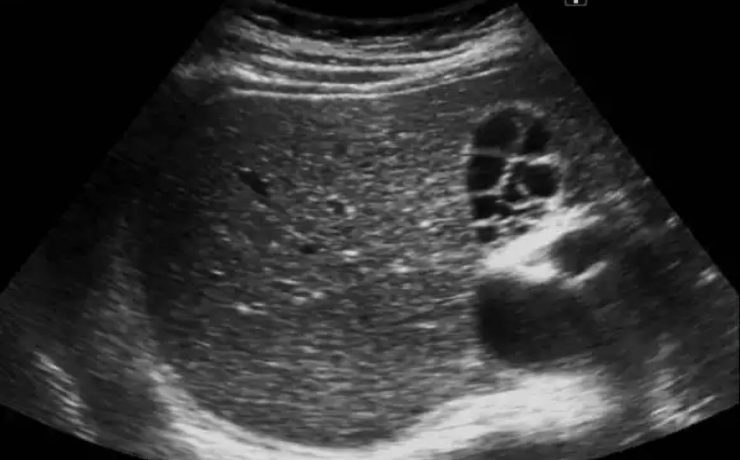

Introducción: El cáncer de endometrio es la segunda neoplasia ginecológica a nivel mundial ,más común en la perimenopausia , la incidencia es de 6 veces mayor en países desarrollados que en los menos desarrollados. La supervivencia en etapas tempranas es del 80%. Estudios de tamizaje Escrutinio a partir de los